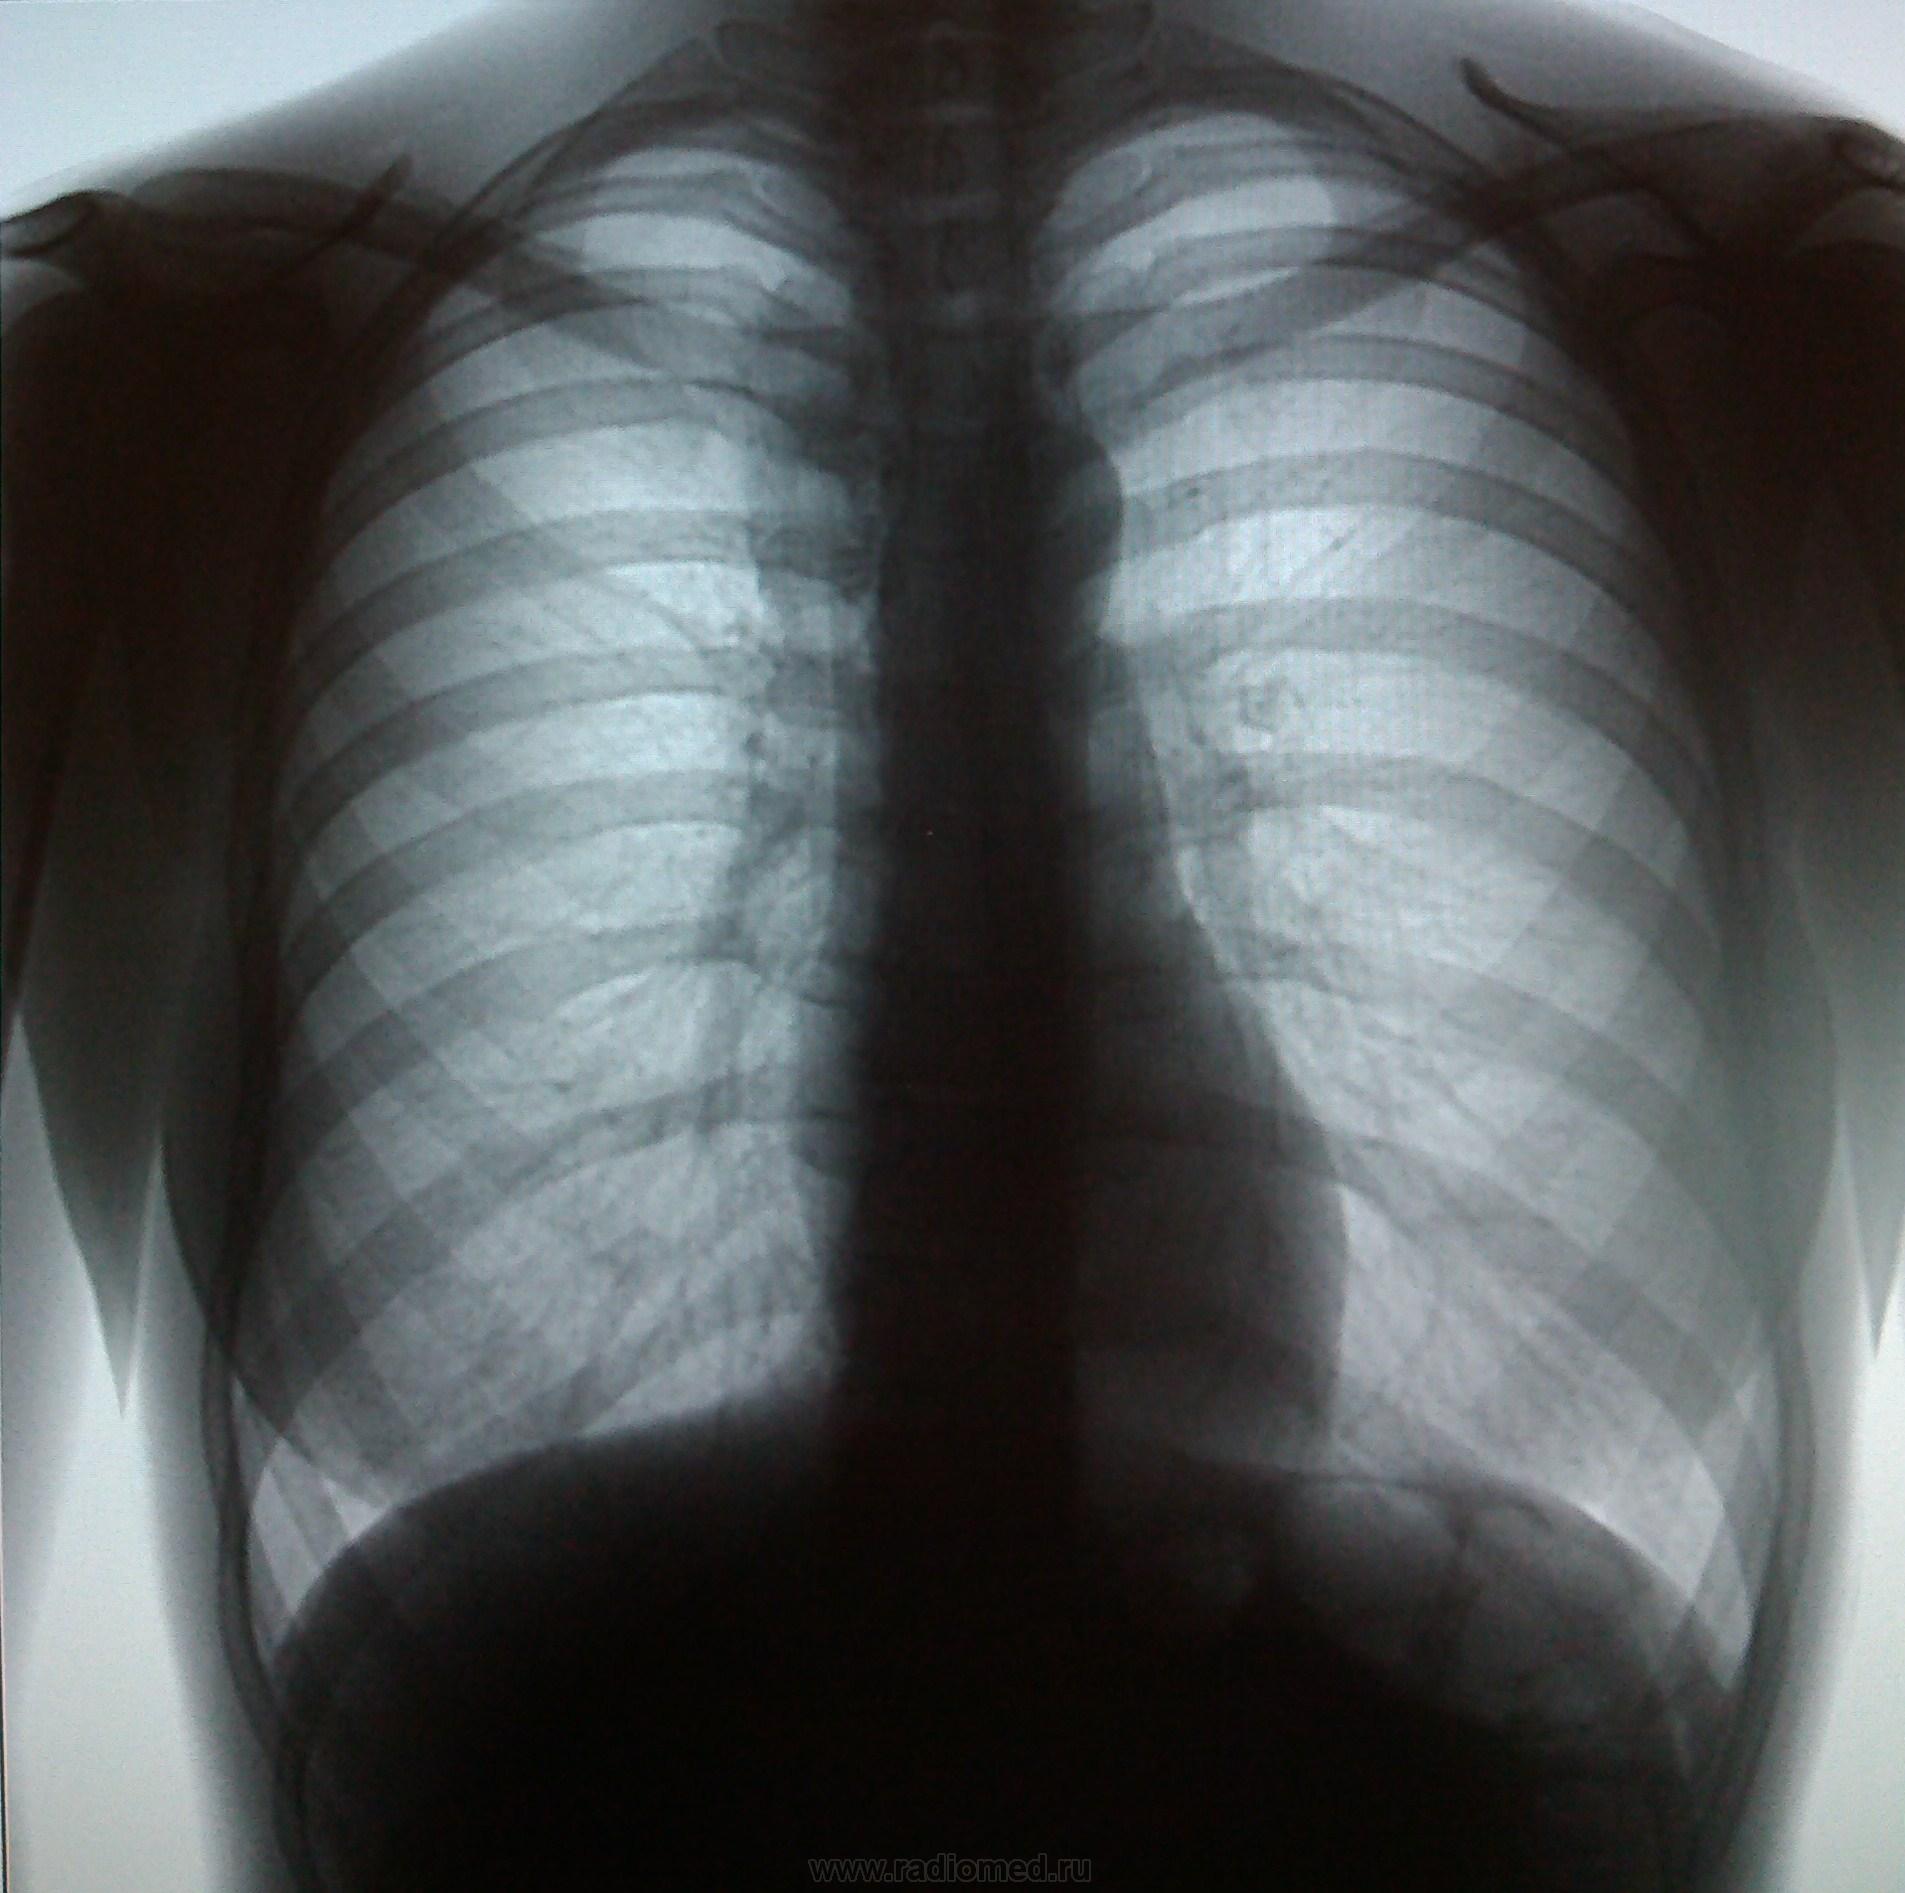

Пол пациента: Женский пол Тип патологии: Другое Область исследования: Грудная клетка и верхние дыхательные пути Методы исследования: Rg Пациентка, 22 года. Мед. осмотр. https://radiomed.ru/sites/default/files/styles/case_slider_image/public/user/18609/img_20130821_111923.jpg?itok=CBCcY0bh ID:30974 Ср, 21/08/2013 - 18:17 #1 Сергей Кузьминов Не на сайте Был на сайте: 1 год 2 месяцев назад Зарегистрирован: 06.10.2012 - 15:51 Публикации: 11813 Обе верхушки томографировать по поводу очаговых теней. Ср, 21/08/2013 - 19:06 #2 maker4ik Не на сайте Был на сайте: 8 лет 9 месяцев назад Зарегистрирован: 19.10.2011 - 17:49 Публикации: 2682 Не вижу патологии. Ср, 21/08/2013 - 21:36 #3 Dr. X-ray Не на сайте Был на сайте: 9 лет 8 месяцев назад Зарегистрирован: 19.07.2013 - 21:06 Публикации: 505 а средостение в верхнем отделе справа не расширено? Ср, 21/08/2013 - 22:20 #4 Сергей Кузьминов Не на сайте Был на сайте: 1 год 2 месяцев назад Зарегистрирован: 06.10.2012 - 15:51 Публикации: 11813 ИМХО Доля непарной вены.А очагульки не получается что-то пометить в пайнте. Ср, 21/08/2013 - 22:57 #5 Nikolas Не на сайте Был на сайте: 1 месяц 26 минут назад Зарегистрирован: 21.12.2010 - 20:37 Публикации: 4560 лимфомы Ходжкина необходимо исключить в первую очередь у молодой женщины. О верификации диагноза прошу сообщить на сайт. Чт, 22/08/2013 - 06:52 #6 Глазков Игорь А... Не на сайте Был на сайте: 11 месяцев 1 неделя назад Зарегистрирован: 19.12.2008 - 20:41 Публикации: 1597 напоминает лимфогранулёматоз. В верхушках лёгких ничего плохого не увидел. Прийди к Себе

Обе верхушки томографировать по поводу очаговых теней.

а средостение в верхнем отделе справа не расширено?

ИМХО Доля непарной вены.А очагульки не получается что-то пометить в пайнте.

лимфомы Ходжкина необходимо исключить в первую очередь у молодой женщины. О верификации диагноза прошу сообщить на сайт.

напоминает лимфогранулёматоз. В верхушках лёгких ничего плохого не увидел.